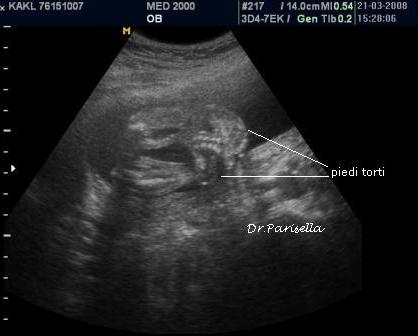

2) artrogriposi caratterizzata principalmente da contratture in flessione;